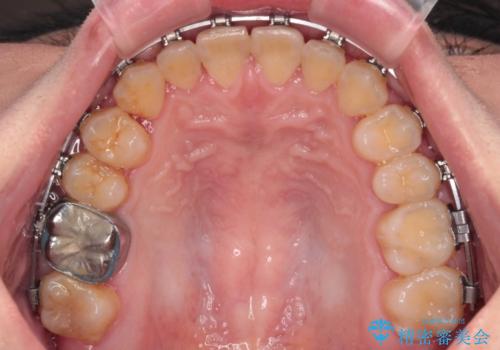

- 矯正装置

- メタルブラケット

- 前歯の反対咬合を気にして来院された患者様です。

当院にて同様の咬み合わせを治療した方からのご紹介ということもあり、ご紹介者と同じワイヤー矯正で早めに治療を終えることを希望されました。

骨格的に下顎が前方に位置していましたが、歯列矯正で改善できると判断し、ワイヤー装置にて矯正治療を行うこととしました。

このような咬み合わせの方の多くは、舌の突出癖が強い傾向にあり、反対咬合改善後に開咬となってしまい、なかなか治療が終わらないことがあります。

こちらの患者様は、舌のトレーニングを治療開始前から徹底的に実践していただき、僅か8ヶ月という短期間で治療を終えることができました。